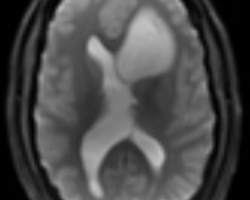

- IRM : coupes axiales, séquences en diffusion B1000, perfusion, T1 et T2 : tumeur hypoT1, hyperT2, peu de diffusion = peu d’œdème, localisation plutôt frontale. Pas de prise de contraste (pas de cliché ici = à compléter) Compte tenu de l’âge, évocateur d’un gliome bas grade. De ce fait, rechercher une comitialité avant tout geste chirurgical.

IRM : lésion basifrontale gauche développée aux dépens du gyrus rectus qui remonte vers l’hypothalamus comprimant les foramens de Monro induisant une probable hydrocéphalie obstructive. Pas de prise de contraste mais séquences en perfusion non exploitables.